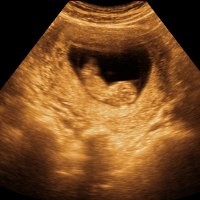

Dominika - Janin yang dikandung oleh seorang ibu harusnya dikeluarkan dari dalam tubuh. Tapi perempuan asal Dominika tidak mengetahui keberadaan janin di dalam perutnya, setelah 30 tahun janin tersebut sudah menjadi mumi.

Seorang perempuan berusia 59 tahun dari Republik Dominika telah menderita sakit perut yang parah selama beberapa dekade, tapi saat itu tidak ada yang tahu apa penyebab pastinya.

Setelah melakukan pemeriksaan X-ray ternyata diketahui bahwa tanpa sadar perempuan tersebut memiliki janin yang sudah mati dan membatu di dalam perutnya selama paling sedikit 30 tahun. Sisa-sisa mumi janin tersebut dikeluarkan dan diketahui memiliki berat 1,686 kg. Hal ini diungkapkan oleh salah seorang pejabat kesehatan Dominika.

Tapi minggu ini ia datang ke rumah sakit umum dengan keluhan rasa sakit yang hebat di daerah perutnya dan saat itulah diketahui ia memiliki janin yang membatu atau anak batu yang kemungkinan berasal dari usia kehamilan 3-5 bulan.

Mumi janin atau janin yang membatu ini memang jarang terjadi, tapi beberapa kasus ditemukan oleh dokter. Dalam istilah medis kondisi ini disebut dengan Lithopedion yang telah dikenal sejak tahun 1557.

Dalam laporan yang dimuat Illinois Medical Journal diketahui bahwa lithopedion adalah janin batu yang dihasilkan dari kehamilan usia 3-4 bulan. Kondisi ini umumnya disebabkan oleh kehamilan ektopik atau hamil di luar rahim.

Pada kehamilan ektopik janin akan melekat di saluran telur dan kemudian tumbuh yang menyebakan beberapa bagian jatuh ke dalam rongga perut. Secara bertahap janin di dalam rongga perut ini akan mengalami pengerasan.